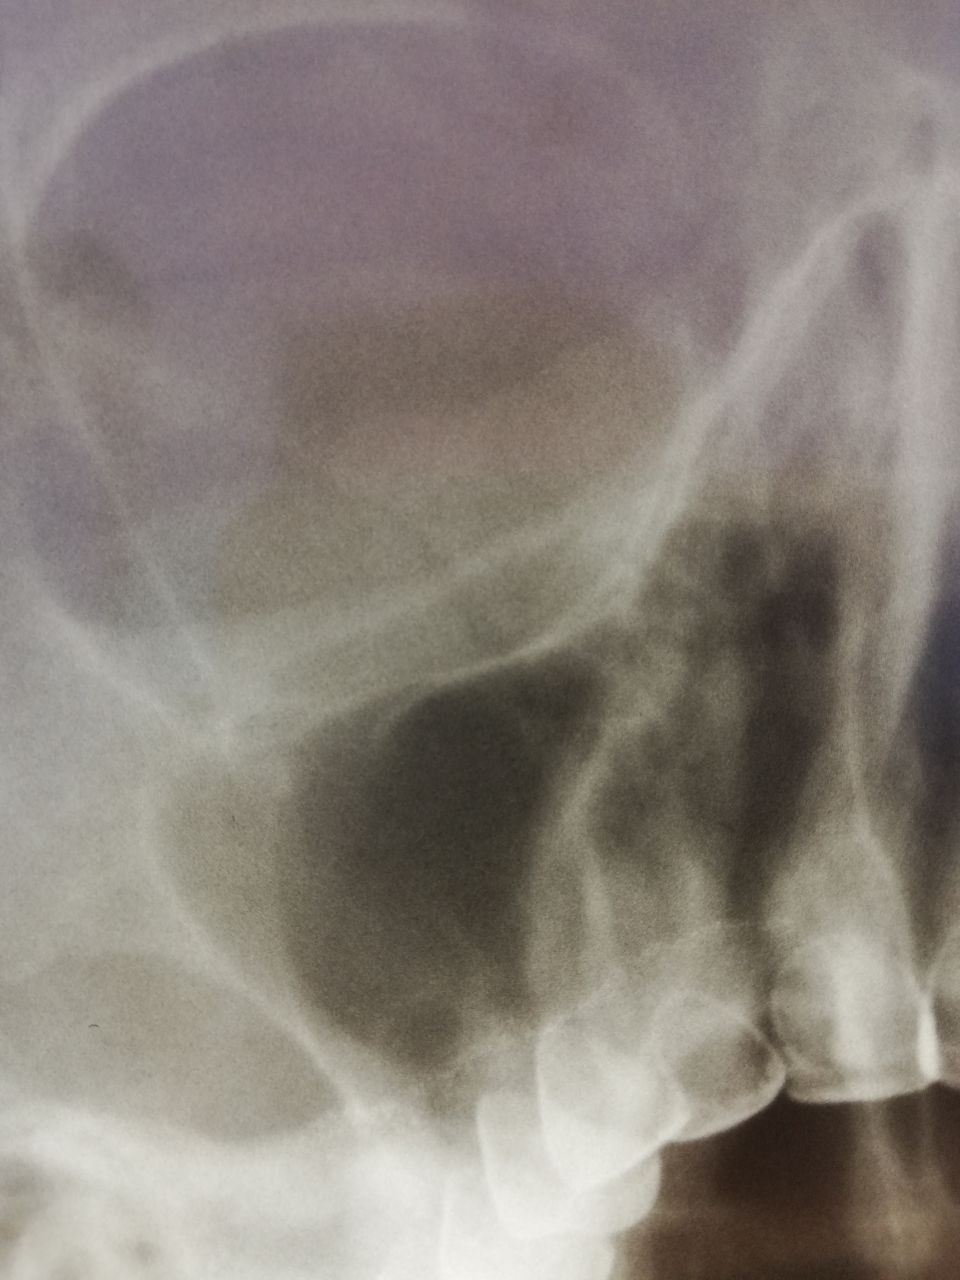

Добрый день, уважаемые коллеги! Женщина, 67 лет, идет на операцию. Есть ли справа синусит? Уплотнение локальное, не по всей стенке, и по форме не очень похоже на отек. Или тут норма и отпустить ее на операцию?

источник

Норма.